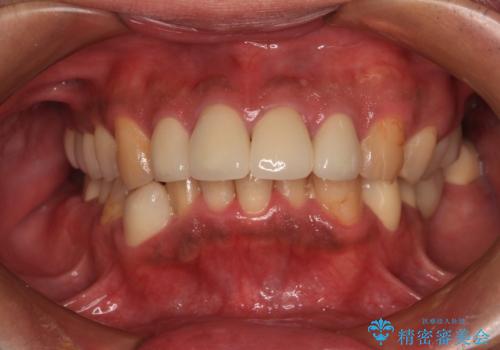

[ 金属アレルギー ] 銀歯を除去するメタルフリー治療

担当医 大元洋佑

![[ 金属アレルギー ] 銀歯を除去するメタルフリー治療の症例 治療前](https://seimitsushinbi.jp/wp/wp-content/uploads/2023/08/e81d14b5b541f23b9fcb9feb23262596-500x350.jpg?v=1692755937)

![[ 金属アレルギー ] 銀歯を除去するメタルフリー治療の症例 治療後](https://seimitsushinbi.jp/wp/wp-content/uploads/2023/08/285add314246a78e4e98332cd6f9956a-500x350.jpg?v=1692755948)